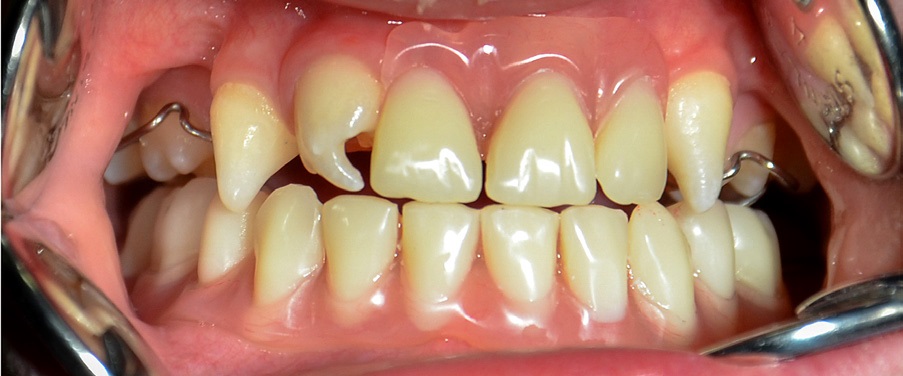

- Opis przypadku.

Braki zębowe u dzieci stanowią poważny problem kliniczny z uwagi na ciągłe zmiany zachodzące w narządzie żucia oraz wzrost i rozwój pacjenta. Rehabilitacja protetyczna pacjentów [...]